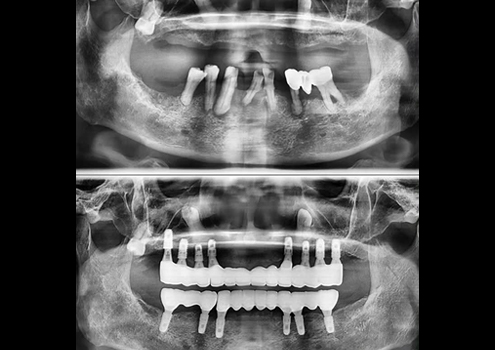

오차없이 정밀한 식립,

디지털 임플란트

파노라마, 3D CT를 이용한 정밀 분석과 모의 수술을 통해

개인의 구강구조와 잇몸뼈에 맞게 식립 위치와 각도,

깊이까지 파악한 후 안전하고 정확하게 수술합니다.